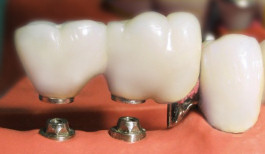

Kronen und Brücken

Jegliche Form von Zahnersatz, ob Krone, Brücke oder Prothese, ist eine Maßanfertigung und wird individuell an Ihre Mundsituation angepasst. Die Praxis arbeitet seit vielen Jahren Hand in Hand mit ortsansässigen deutschen Meisterfachlaboren für Zahntechnik.

Die Brücke: Zahnersatz für Zahnlücken

Damit die Kaufunktion erhalten bleibt, müssen Zahnlücken geschlossen werden. Keramik-Brücken stellen dabei eine besonders elegante Lösung dar. Die Nachbarzähne werden überkront und dienen als Brückenpfeiler.

Ist die Lücke zu groß, kann ein Implantat als zusätzlicher Brückenpfeiler nötig sein, damit die Versorgung den Druckbelastungen beim Essen standhält. Eine Brücke stellt das natürliche Aussehen und die volle Funktion einer intakten Zahnreihe wieder her, unterstützt gutes Kauen und richtiges Sprechen und stabilisiert den Halt der übrigen Zähne im Kiefer.

Brücke aus Keramik